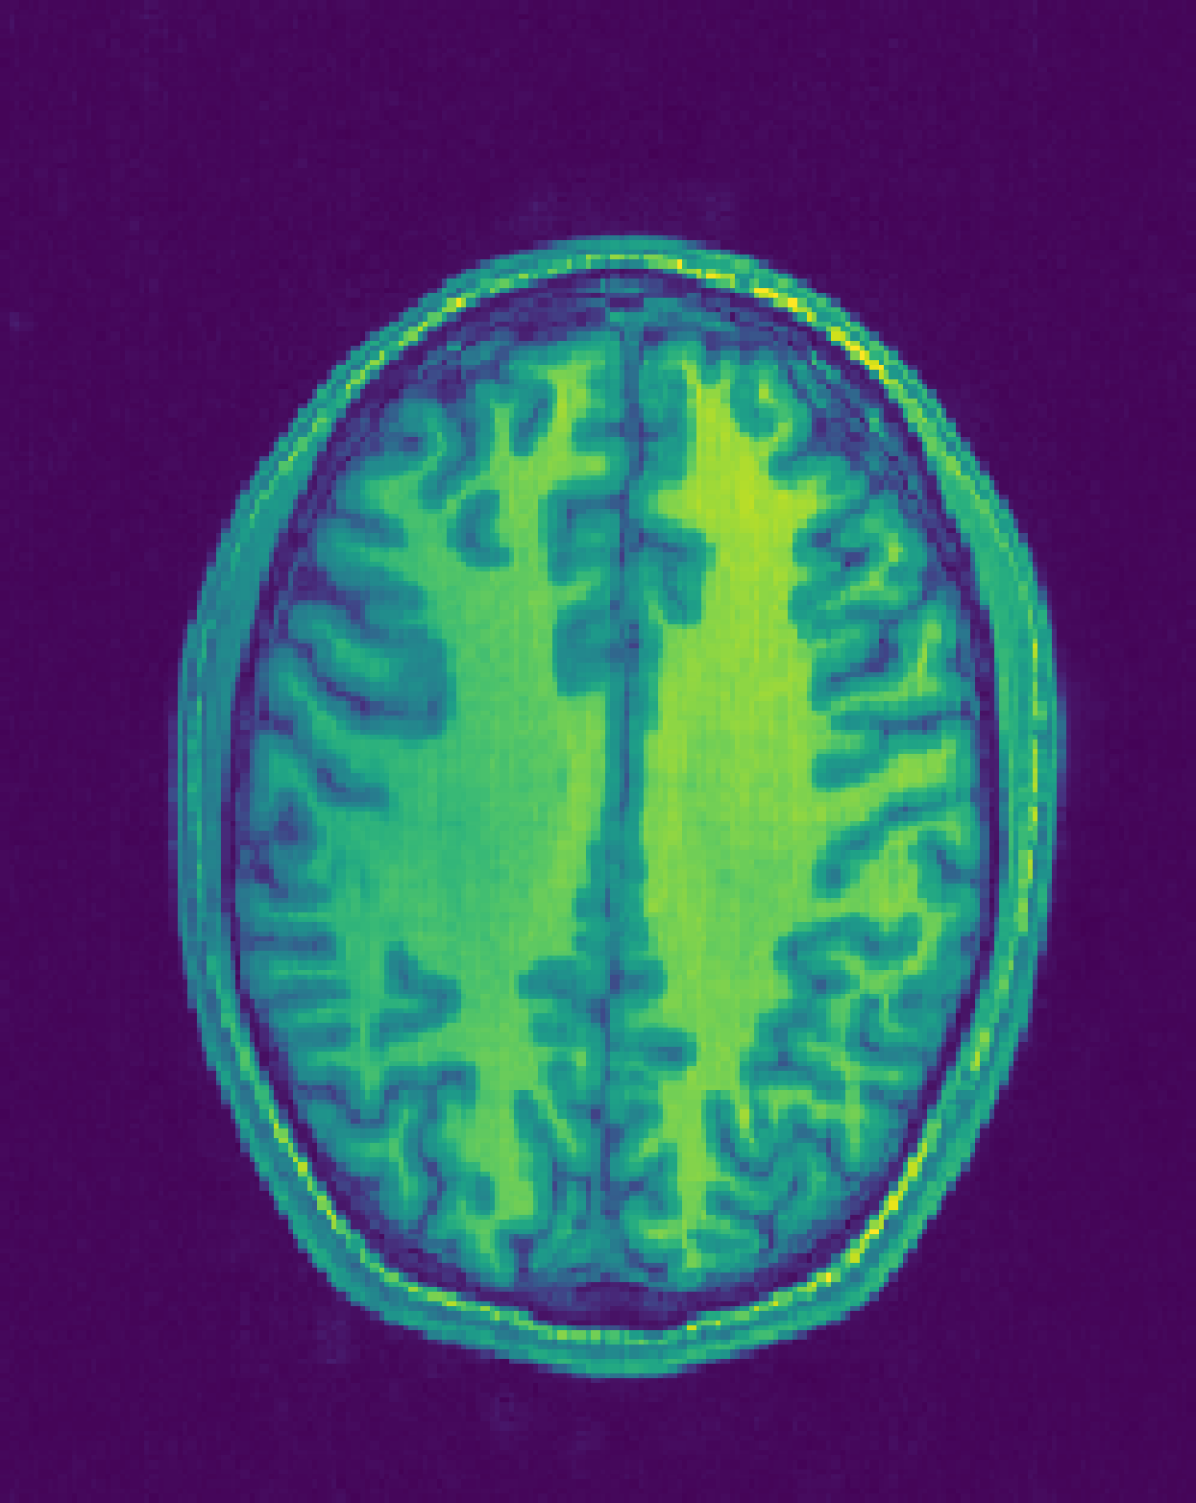

Figure 1: Reconstruction results for R = 3, with (1(a)) the fully sampled image, (b) the zero-filled image, (c) the reconstruction with no bias field estimation, (d) the joint reconstruction with bias field estimation using N4. The first three rows show reconstruction results for an HCP image, its zoomed-in version and the corresponding bias field. The next three rows show results for an in-house measured image. For visualization purposes, MR images are clipped to [0, 1.2] and bias fields, to [0.5, 1.8].

The quantitative improvement is also supported by the visual inspection of the images given in Figure 1. From the HCP image, one can observe that the level of artifacts is reduced with the proposed method. This becomes more evident in the zoomed-in images. The red arrow points to a part of the image where the proposed method can reconstruct the structures faithfully, whereas the baseline method struggles. Aliasing artifacts are globally suppressed better with the joint reconstruction method. Similarly, for the in-house measured image, the grey matter structure that the red arrow points to is not reconstructed in the baseline method, whereas it again appears with the proposed method.